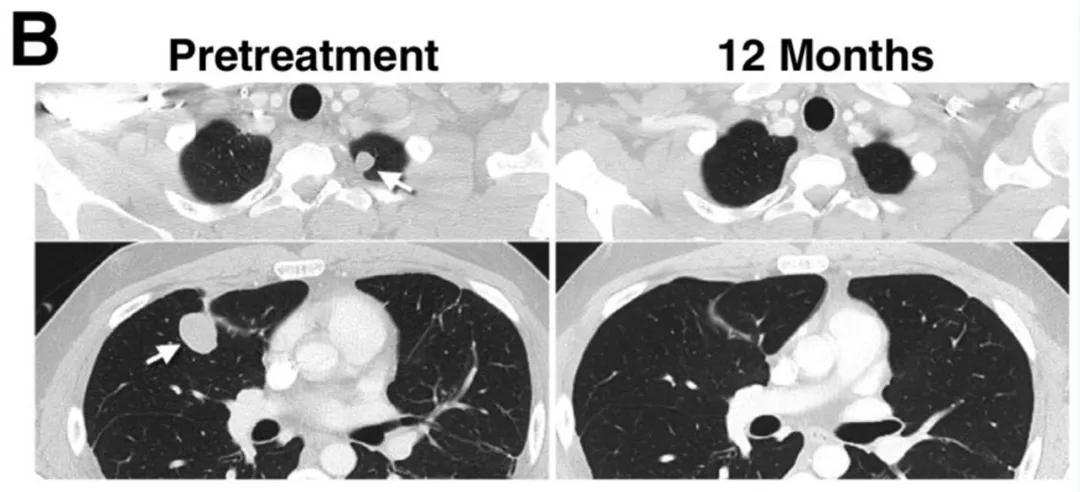

15号患者所有转移灶(含肺部多发转移灶)完全消退,疗效维持1年以上(详见下图B)。